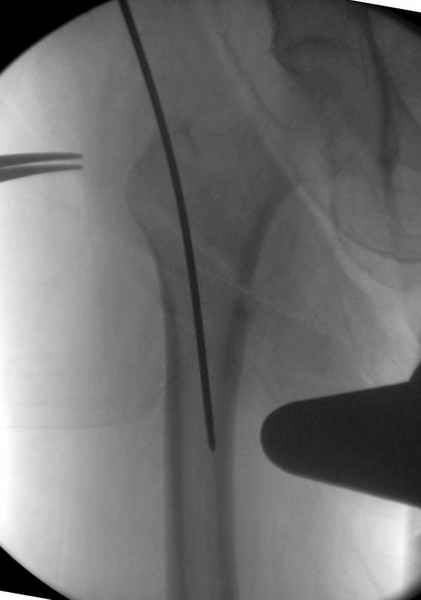

Изначально у оперируещего хирурга были только теоретичесике представления о ЗИМО с блокированием, планировался компрессионно-динамический остеосинтез стержнем S2 (Stryker).

Во время операции ни стол ортопедический,ни ДРУ не применялось (думалось, что сделают все на руках!)

Изначально была выбрана не правильная точка введения стержня, в связи с чем в конце, я подчеркну, в конце операции произошло из-за напряжения между прокимальным концом канала бедра и стержнем разрушение в/3 бедра.

Под ЭОП во время операции такого смещения не было. Мы бы конечно не отпустили этого больного с такой картиной (сами бы что-то сделали или к вам отпр).